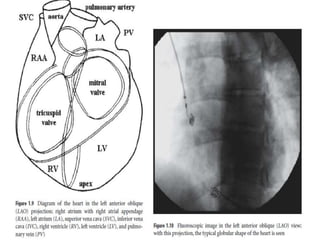

Anatomy of RA •Components – RA appendage – Venous part – Vestibule, inferiorly near TV annulus – Septum – Sulcus Terminalis / Crista separates RAA and venous part – Sinus node situated in the Sulcus terminalis at SVC – RA junction

• 31.

• 32.

Anatomy of RA- RAO view